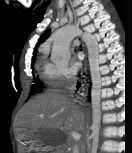

- 多项选择题患者,男性, 8岁,发绀、气促, 易感冒,彩超提示只见一个心室, CT检查如图所示,请选择正确的选项 ( )